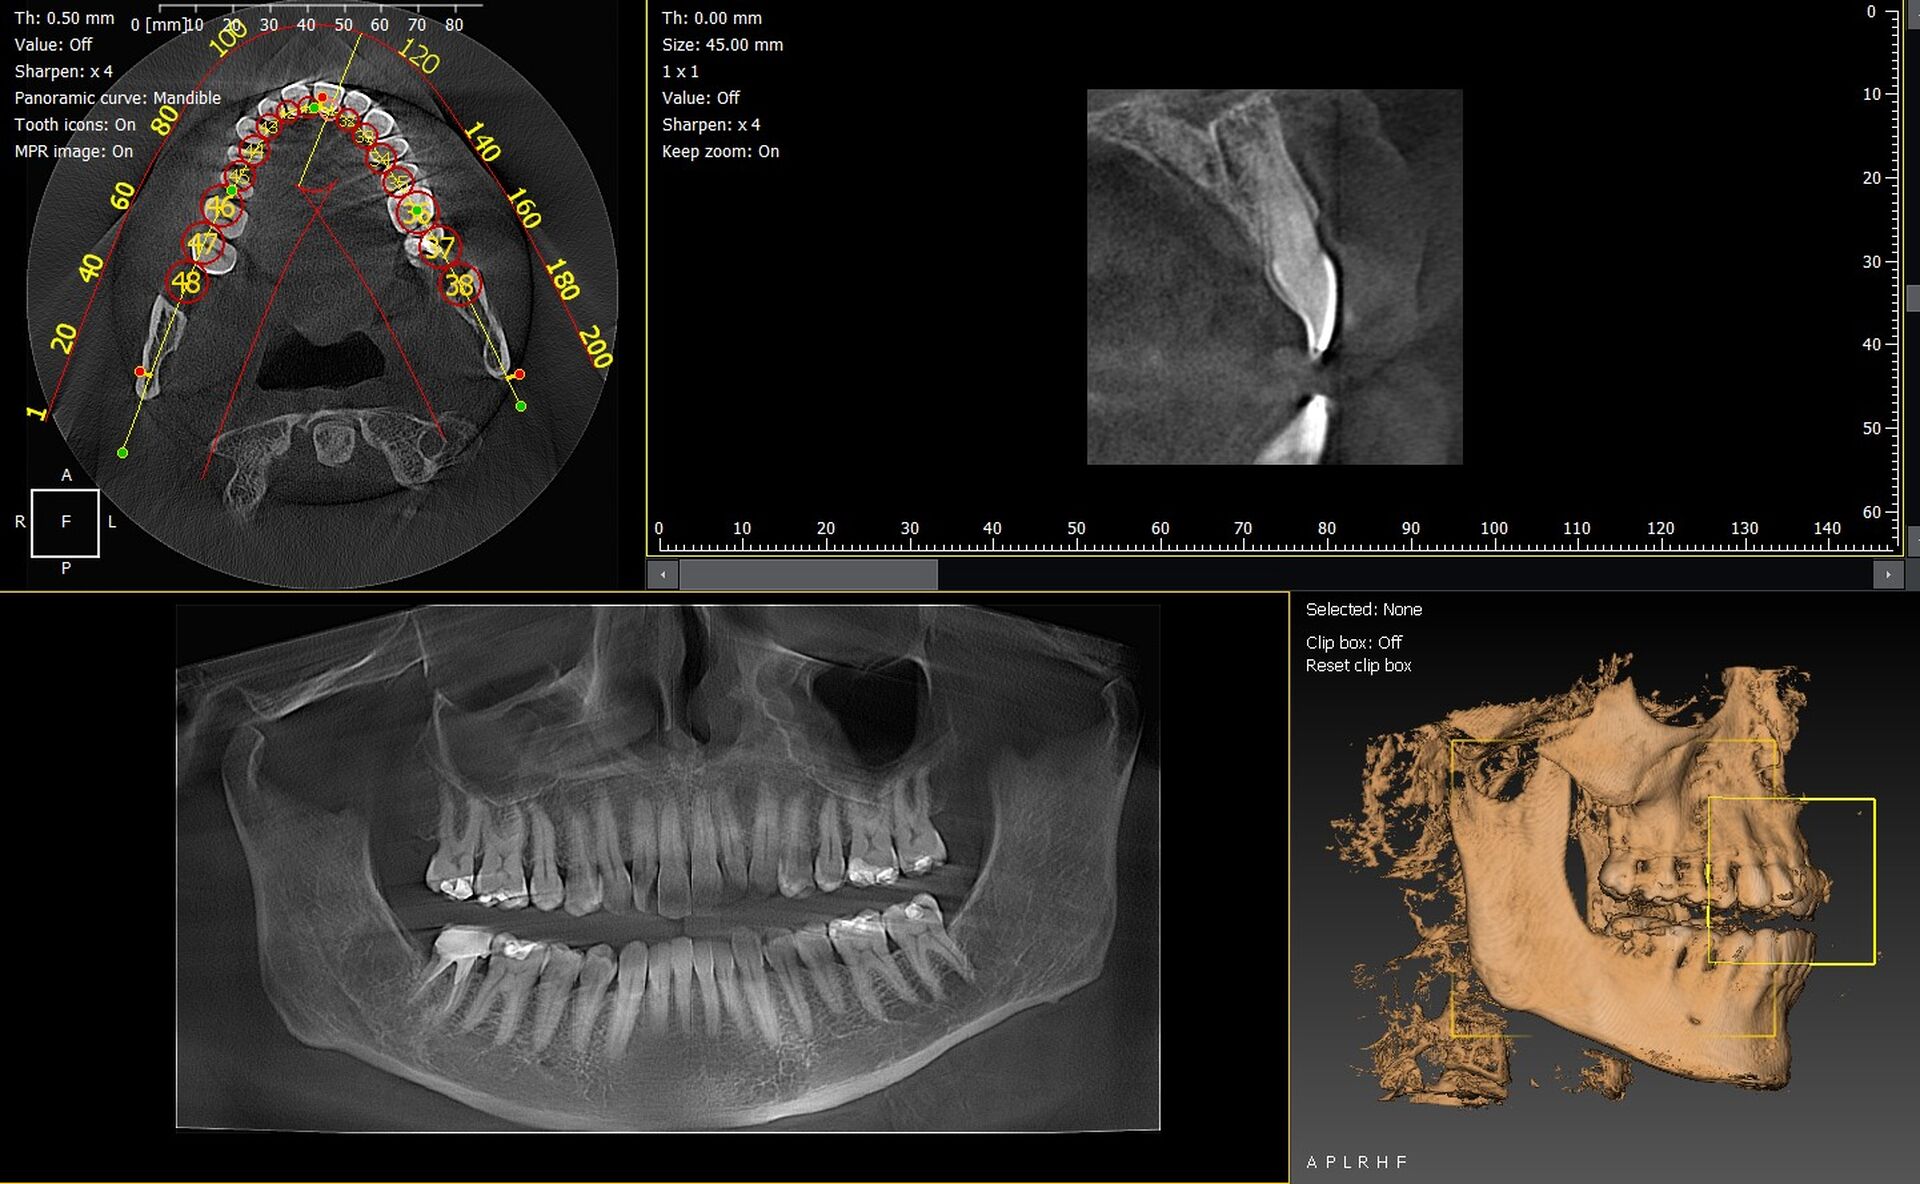

Les cabinets dentaires d’Embrun et des Hautes Alpes 05 recherchent aujourd’hui des solutions d’imagerie 3D fiables, précises et adaptées à une activité clinique exigeante. Les technologies CBCT offrent un diagnostic plus sûr, une planification implantaire optimisée et une interprétation immédiate des structures anatomiques. Parmi les équipements les plus performants du marché, les gammes Durr Dental VistaVox et Owandy I-Max 3D se distinguent par leur qualité d’image, leur ergonomie et leur simplicité d’intégration dans les cabinets d’Embrun.

Panoramique CBCT 3D Durr Dental VistaVox : précision et champ diagnostique élargi

Le VistaVox de Durr Dental est reconnu pour son volume d’acquisition adapté à l’arcade complète, permettant une visualisation parfaite des zones postérieures. Sa technologie de reconstruction optimise le positionnement du patient et garantit une lecture claire des canaux mandibulaires, sinus et zones anatomiques complexes.

• Volume 3D optimisé pour diagnostics implantaires.

• Images haute résolution avec faible dose de rayons.

• Positionnement patient simplifié pour un gain de temps.

• Intégration fluide avec les logiciels métiers dentaires existants.